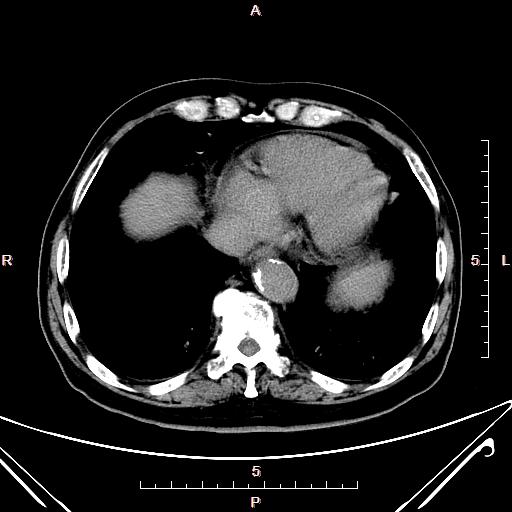

CT50811:上腹部CT

男,88岁,腹痛1个月,加重8小时,10年前胆囊切除,彩超示:肝内外胆管扩张。

1、胆总管及肝内胆管扩张并于胰头钩突部截断,多考虑胆总管占位性病变,建议ERCP或MRCP。

2、双肾囊肿。

胆总管末端占位